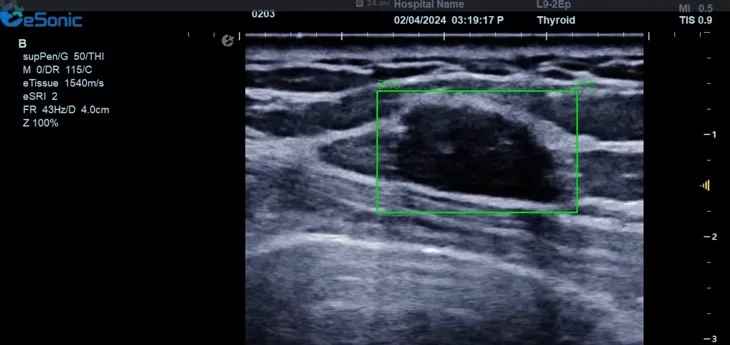

百乐博平台医疗(ESI)表示,其最新的人工智能功能可以帮助到医疗机构的工作效率,功能包括,实时、动态、快速自动识别病灶,良恶性病灶概率预测,甲状腺结节和乳腺的二维灰阶动态自动实时检测需求,提供多个结节动态检测轮廓框。实时获取多幅具备临床特征(大小、属性等)的结节切面,同时提供当前切面所示结节的结节大小、属性特征、TI-RADS 分级。

对于甲状腺结节相关的自动检测功能,甲状腺结节病灶检出率≥95%,良恶性分类灵敏度≥90%、良恶性分类特异度≥85%。